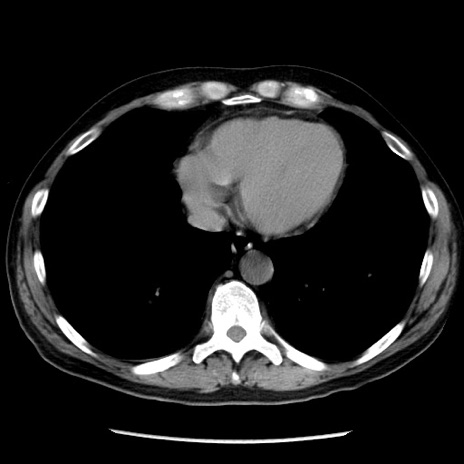

症例29(横断像)

【症例】40歳代男性

【現病歴】2日前から胃痛あり。徐々に周期的な激痛に変化した。本日になっても激痛があるため受診。

【身体所見】意識清明、BT 38-39℃台あり、腹部:膨満、やや硬、右下腹部に圧痛あり。

【データ】WBC 8500、CRP 23.26